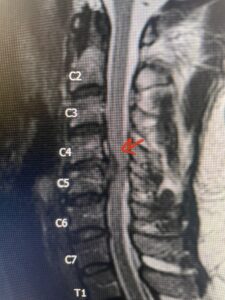

This 47-year-old male who four months prior was lifting weights developed sharp pain in his neck. After that he developed progressive numbness in his arms, neck pain and headache. He said that the right arm was worse than the left. On examination the patient had long tract weakness on the right side which included his triceps, finger extensors, hip flexors, and dorsiflexors. The patient did not have hyperreflexia. MRI (Fig. 2) demonstrated a massive, extruded disc herniation with severe cord compression. The patient because of progressive myelopathy and spinal cord compression was indicated for anterior cervical discectomy and fusion at C4-5 (Fig. 3). Patient had significant improvement of weakness and numbness post operatively.

Fig. 2a Sagittal T2-weighted cervical MRI demonstrating large C4-5 herniated disc with spinal cord compression (red arrow)

Fig: 2b Axial T2-weighted cervical MRI demonstrating spinal cord compression from C4-5 herniated disc (red arrow)